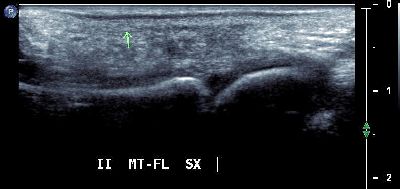

Esostosi prima testa metatarsale esostosi metatarsale